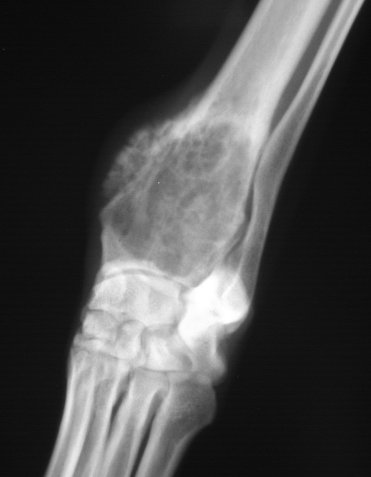

Первый шаг - рентген. Особые положения для снимков могут быть критическими для обнаружения опухолей, появляющихся в местах, отличных от аппендикулярного скелета. Ректальный осмотр является также очень важным, при этом особое внимание уделяется мочеполовой системе, чтобы исключить наличие первичной опухоли.

Биопсия обязательна, потому что в начальных стадиях опухолевые клетки сложно обнаружить на снимках. Другой возможной причиной могут быть грибковые инфекции кости, симптомы которых подобны остеосаркоме. Биопсия кости может быть выполнена открытым способом, закрытым или с помощью иглы. Преимущество открытого метода состоит в том, что может быть изъято большое количество материала, который сделает гистопатологический диагноз более точным.

Рентгеновское обследование костей может быть полезным методом для обнаружения и локализации костных метастазов у собак.